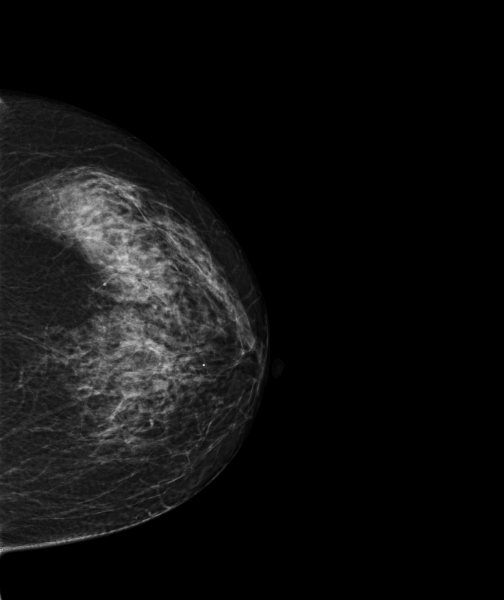

Case of the week (week 51, 2022)

MammoScreen® points to developing asymmetry of the right breast.